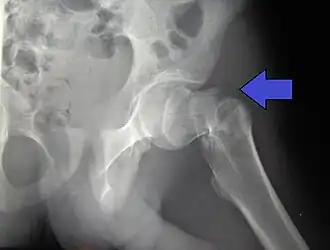

Fratura intertrocantérica da anca em homem de 17 anos

TiposIntracapsular, extracapsular (intertrocantérica, subtrocantérica, grande trocânter, pequeno trocânter)[1]